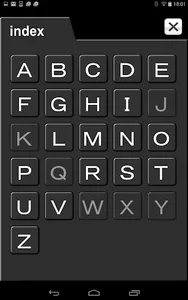

This is the Ultimate Solution for Human Anatomy in CT / MRI Cross-Section! This enables you to find out terminology by pointing an anatomical area with finger cursor. By clicking a word from Index, you can highlight a location of the anatomy in every picture. The first release is most popular Brain MRI version! It displays brain territories, detailed anatomies as well as major anatomies simultaneously, which contains 22 slices of MRI pictures and 150 terminologies with both T1-weighted and T2-weighted images. As you shift image slices, you will be able to realize a vivid image of comprehensive anatomy and gain an excellent understanding of anatomy. Enjoy learning anatomies with this powerful tool! Find out how a single anatomy appears on each picture! We guarantee that not only learners but also physicians, medical workers, researchers and educators will find out the ease of use! This is an Ultimate app of interactive CT/MRI atlas for Android users!

This is the Ultimate Solution for Human Anatomy in CT / MRI Cross-Section! This enables you to find out terminology by pointing an anatomical area with finger cursor. By clicking a word from Index, you can highlight a location of the anatomy in every picture. The first release is most popular Brain MRI version! It displays brain territories, detailed anatomies as well as major anatomies simultaneously, which contains 22 slices of MRI pictures and 150 terminologies with both T1-weighted and T2-weighted images. As you shift image slices, you will be able to realize a vivid image of comprehensive anatomy and gain an excellent understanding of anatomy. Enjoy learning anatomies with this powerful tool! Find out how a single anatomy appears on each picture! We guarantee that not only learners but also physicians, medical workers, researchers and educators will find out the ease of use! This is an Ultimate app of interactive CT/MRI atlas for Android users!